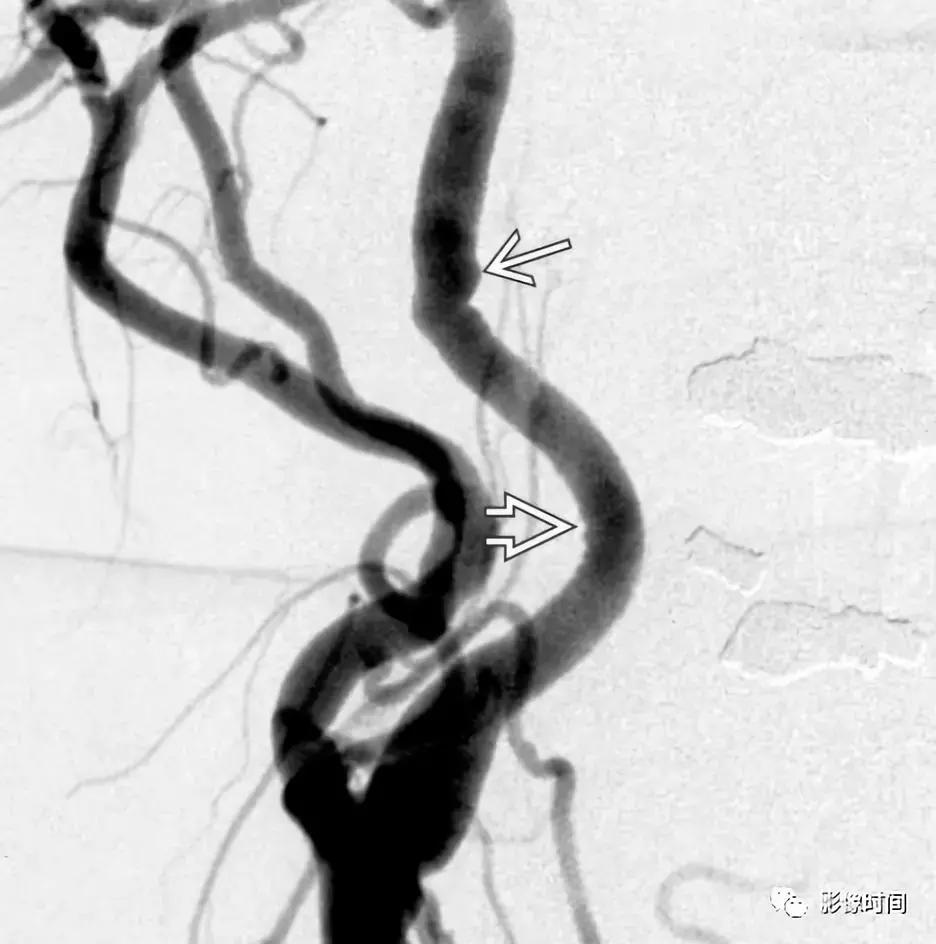

6.纤维肌性发育不良:颈动脉纤维肌性发育不良是一种罕见且无症状的疾病,因此往往是偶然发现的。然而,有症状的病人可以出现脑梗死、短暂缺血、或蛛网膜下腔出血。虽然纤维肌性发育不良可发生在三层动脉壁中的任何一层,但中膜受累是最常见的表现。超过 90% 的病例动脉壁由于纤维增厚和弹性层的破坏而而导致多灶性狭窄和扩张。值得注意的是管腔扩张往往大于正常血管直径,从而有助于区分纤维肌性发育不良和动脉粥样硬化。「串珠」外观在 80% -90% 的病例中都能看到。CTA 和 MRA 是首选检查。

模式图显示纤维肌性发育不良的主要亚型:1 型表现为收缩和扩张的交替;2 型表现为管状狭窄,3 型表现为局灶性波纹+憩室。MRA 显示双侧颈内动脉「串珠」外观(箭头)。CTA 和 DSA 亦显示颈内动脉「串珠」外观。